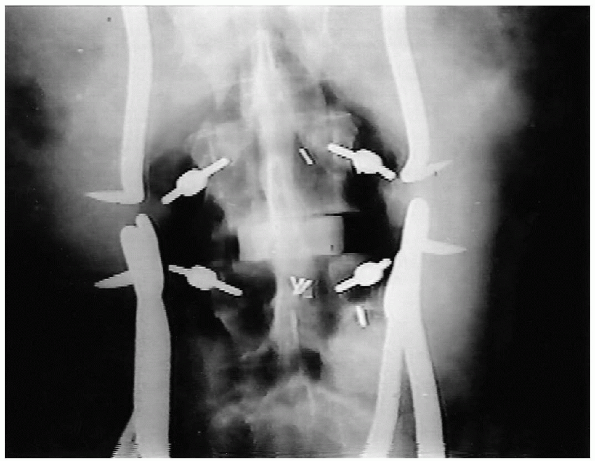

radiographic evaluation is done before continuing (Fig. 19-23).

Next, a flexible ball-tipped probe is placed into the pedicle and all

deep endpoint. Radiopaque marker pins can be placed into the pedicle

holes and an intraoperative radiograph or fluoroscopic image can be

obtained to confirm intrapedicular positioning of the markers (Fig. 19-24). Following this, the pedicle hole may be tapped, and the screw inserted (Figs. 19-25 and 19-26).

![]() |

FIGURE 19-23. Intraoperative anteroposterior x-ray film with markers in pedicles of L3 and L4.